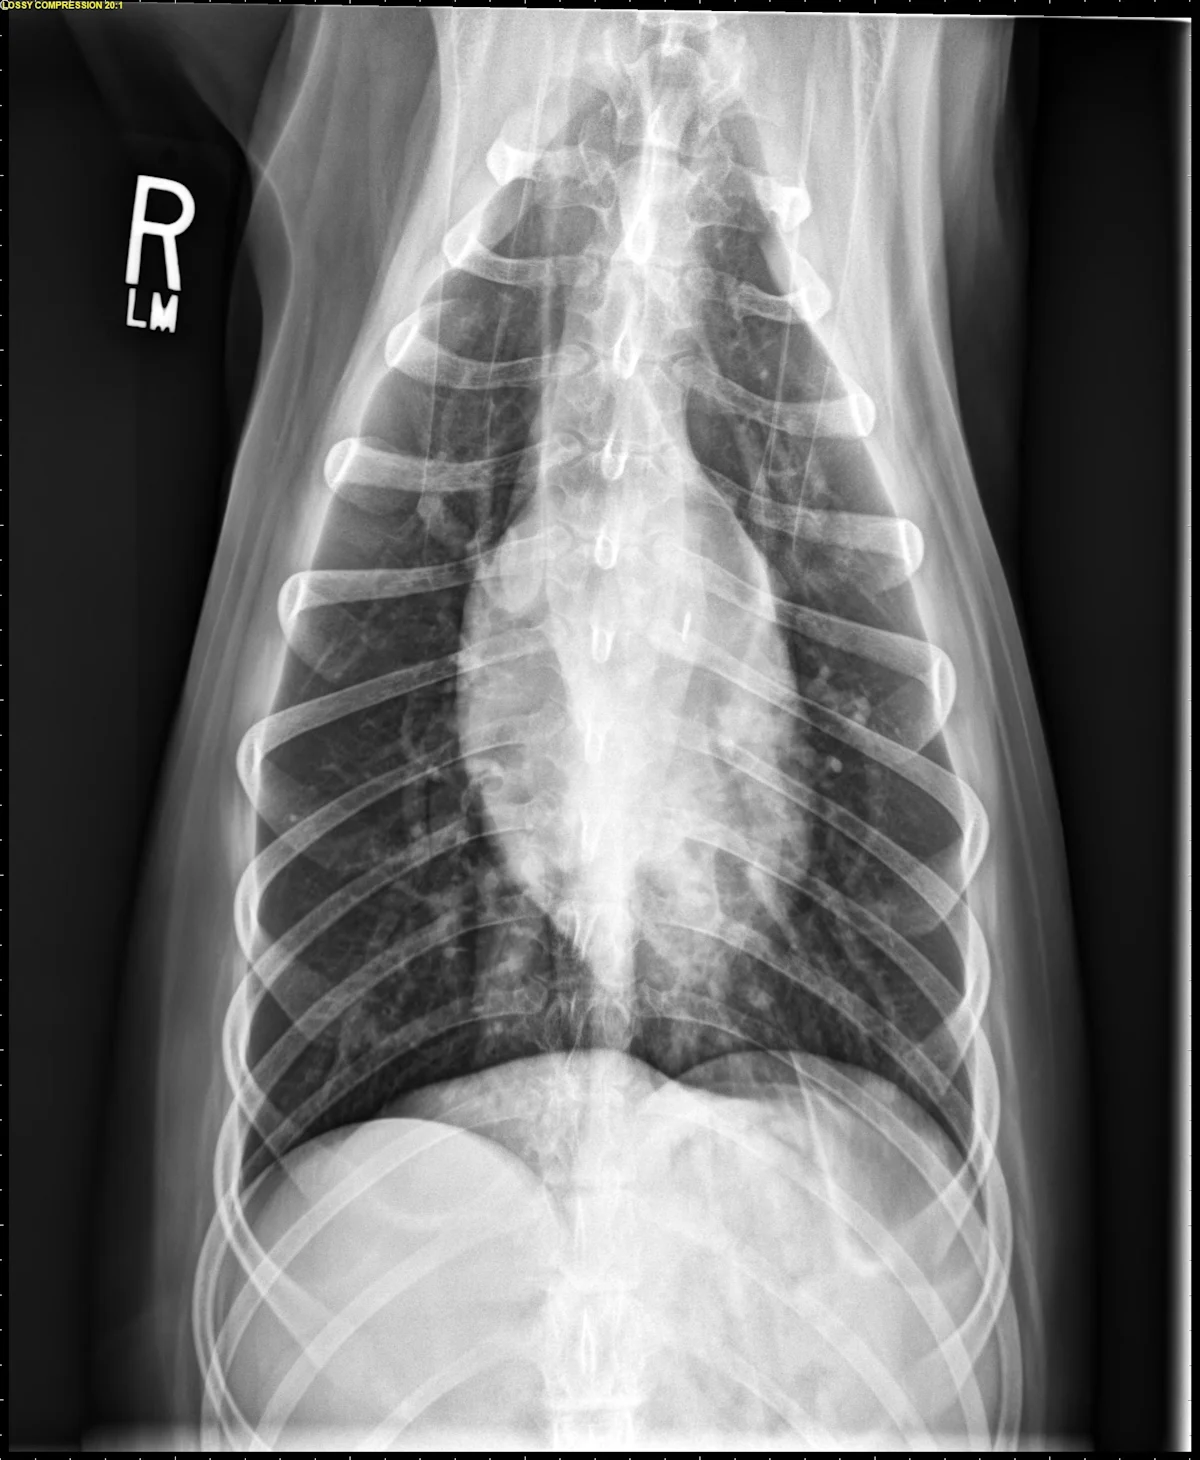

At least 2 orthogonal views, ideally taken during peak inspiration, are necessary for appropriate radiographic study of the cardiovascular system; however, a 3-view study is ideal for comprehensive evaluation of the thorax. Some differences should be considered when deciding to acquire a right versus left lateral projection and a dorsoventral (DV) versus ventrodorsal (VD) projection. On the left lateral view, the cardiac silhouette is typically more rounded and the apex is further elevated from the sternum than in the right lateral view (Figure 1). In the DV view, the cardiac silhouette is commonly displaced cranially and to the left by the diaphragm and appears more rounded than in the VD view. The caudal pulmonary vasculature is better delineated in the DV view, whereas the lung field (particularly the accessory lobe) is better evaluated in the VD view (Figure 2).

FIGURE 2 Normal DV (left) and VD (right) projections of the thorax in a large, crossbreed dog. The cardiac silhouette appears more rounded, and the caudal pulmonary vasculature is more apparent (arrowheads) in the DV view compared with the VD view. In some DV projections, the cardiac silhouette can appear significantly displaced to the left (not apparent in this case). Images courtesy of Federico Villaplana Grosso, DACVR, DECVR